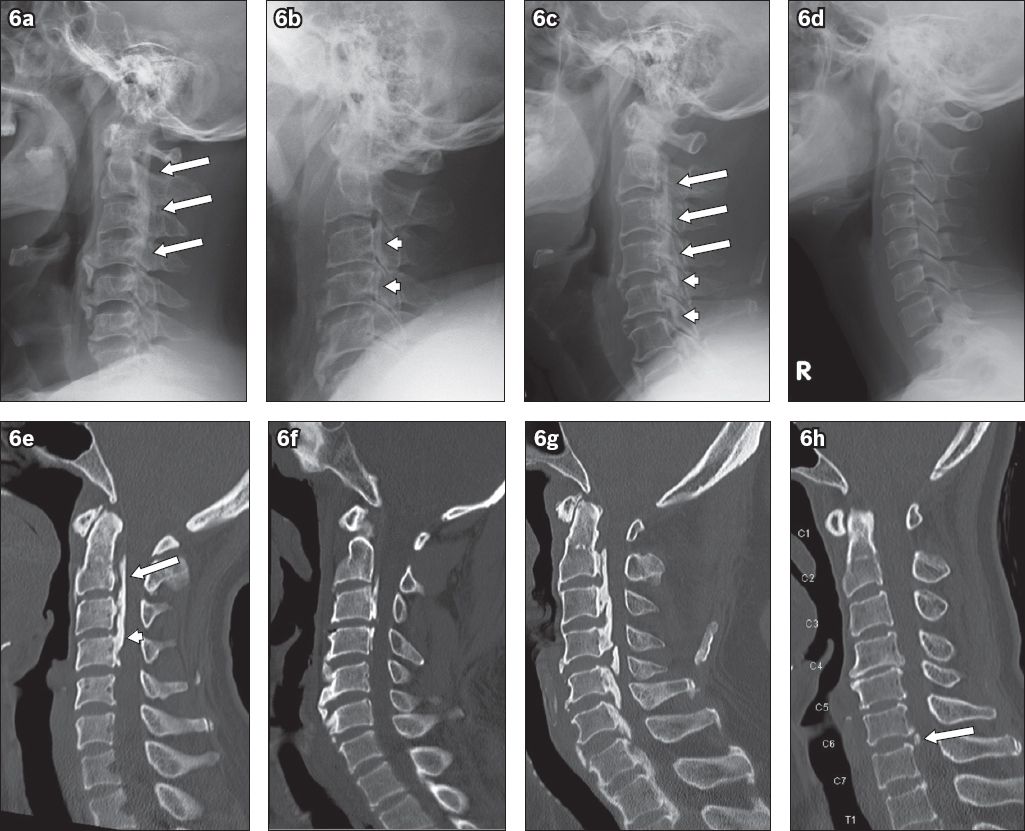

Fig. 4

(a) Sagittal T2-W postoperative MR image shows improvement in spinal canal stenosis and reduction in intramedullary T2-W signal. (b) Preoperative and (c) postoperative axial T2-W MR images at level C3/4 show improvement in central spinal canal stenosis after laminoplasty. Note the reappearance of cerebrospinal fluid posterior to the spinal cord post-surgery (* in c).